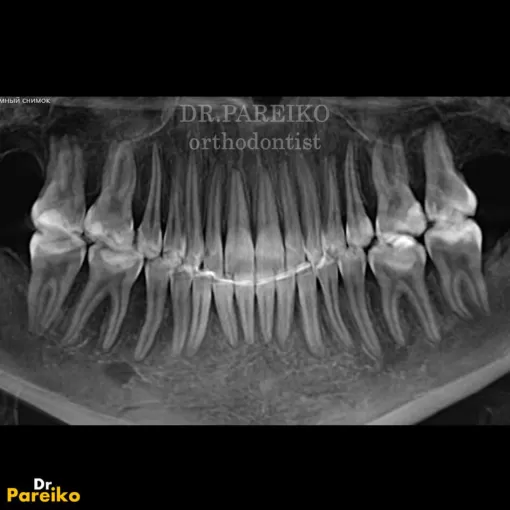

Эндодонтическое лечение с использованием микроскопа

По данным КЛКТ в области зуба 4.6 был выявлен воспалительный очаг. Проведено эндодонтическое лечение с использованием микроскопа, с последующим протезированием коронкой из диоксида циркония.